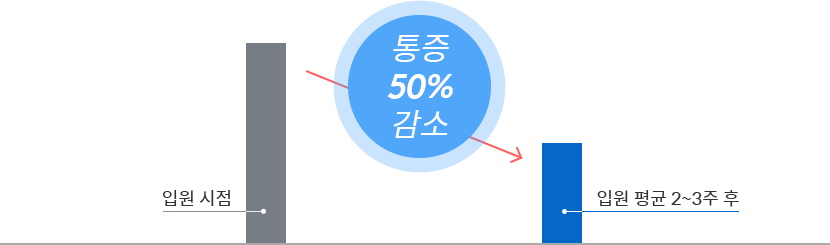

022주 입원집중치료를 통해 통증 50% 이상 감소

허리디스크* 평균입원 2~3주 기준

목디스크* 평균입원 2~3주 기준